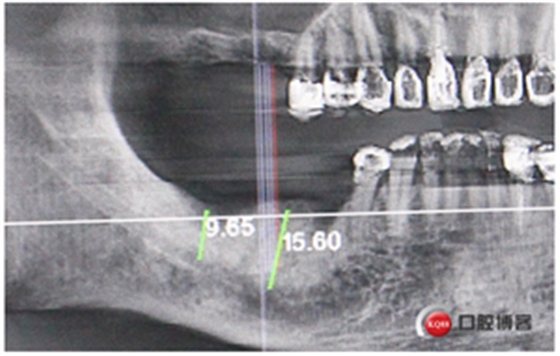

中年男性,右上右下后牙缺失,上頜竇底骨高度3mm,身體健康無不良習(xí)慣。

計劃:1.右上6,7外提升同期植入植體